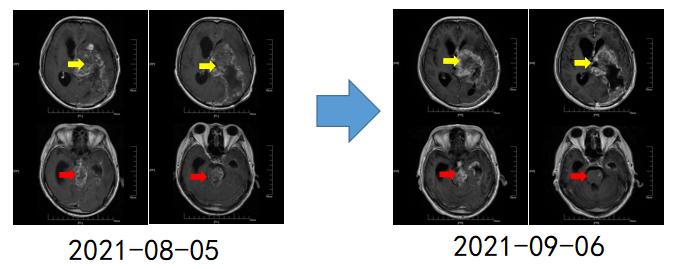

患者乙,2019年2月诊断为胶质母细胞瘤复发WHO IV级,多家医院拒绝为其手术,7月远赴德国治疗。一年后,多肿瘤再次复发。于今年6月在外院行脑肿瘤切除术,术后病理提示复发胶质母细胞瘤,患者为求进一步诊治来我院就诊。经过我院胶质瘤多学科专家会诊后考虑患者为胶质母细胞瘤晚期,结合患者一般情况,放射治疗条件不允许,遂建议患者予以CAR-T细胞回输,回输后患者症状明显改善,目前在我院持续治疗中。

【图2.典型病例二:患者在MDT门诊就诊后,接受CAR T细胞回输治疗,治疗后肿瘤较前缩小】